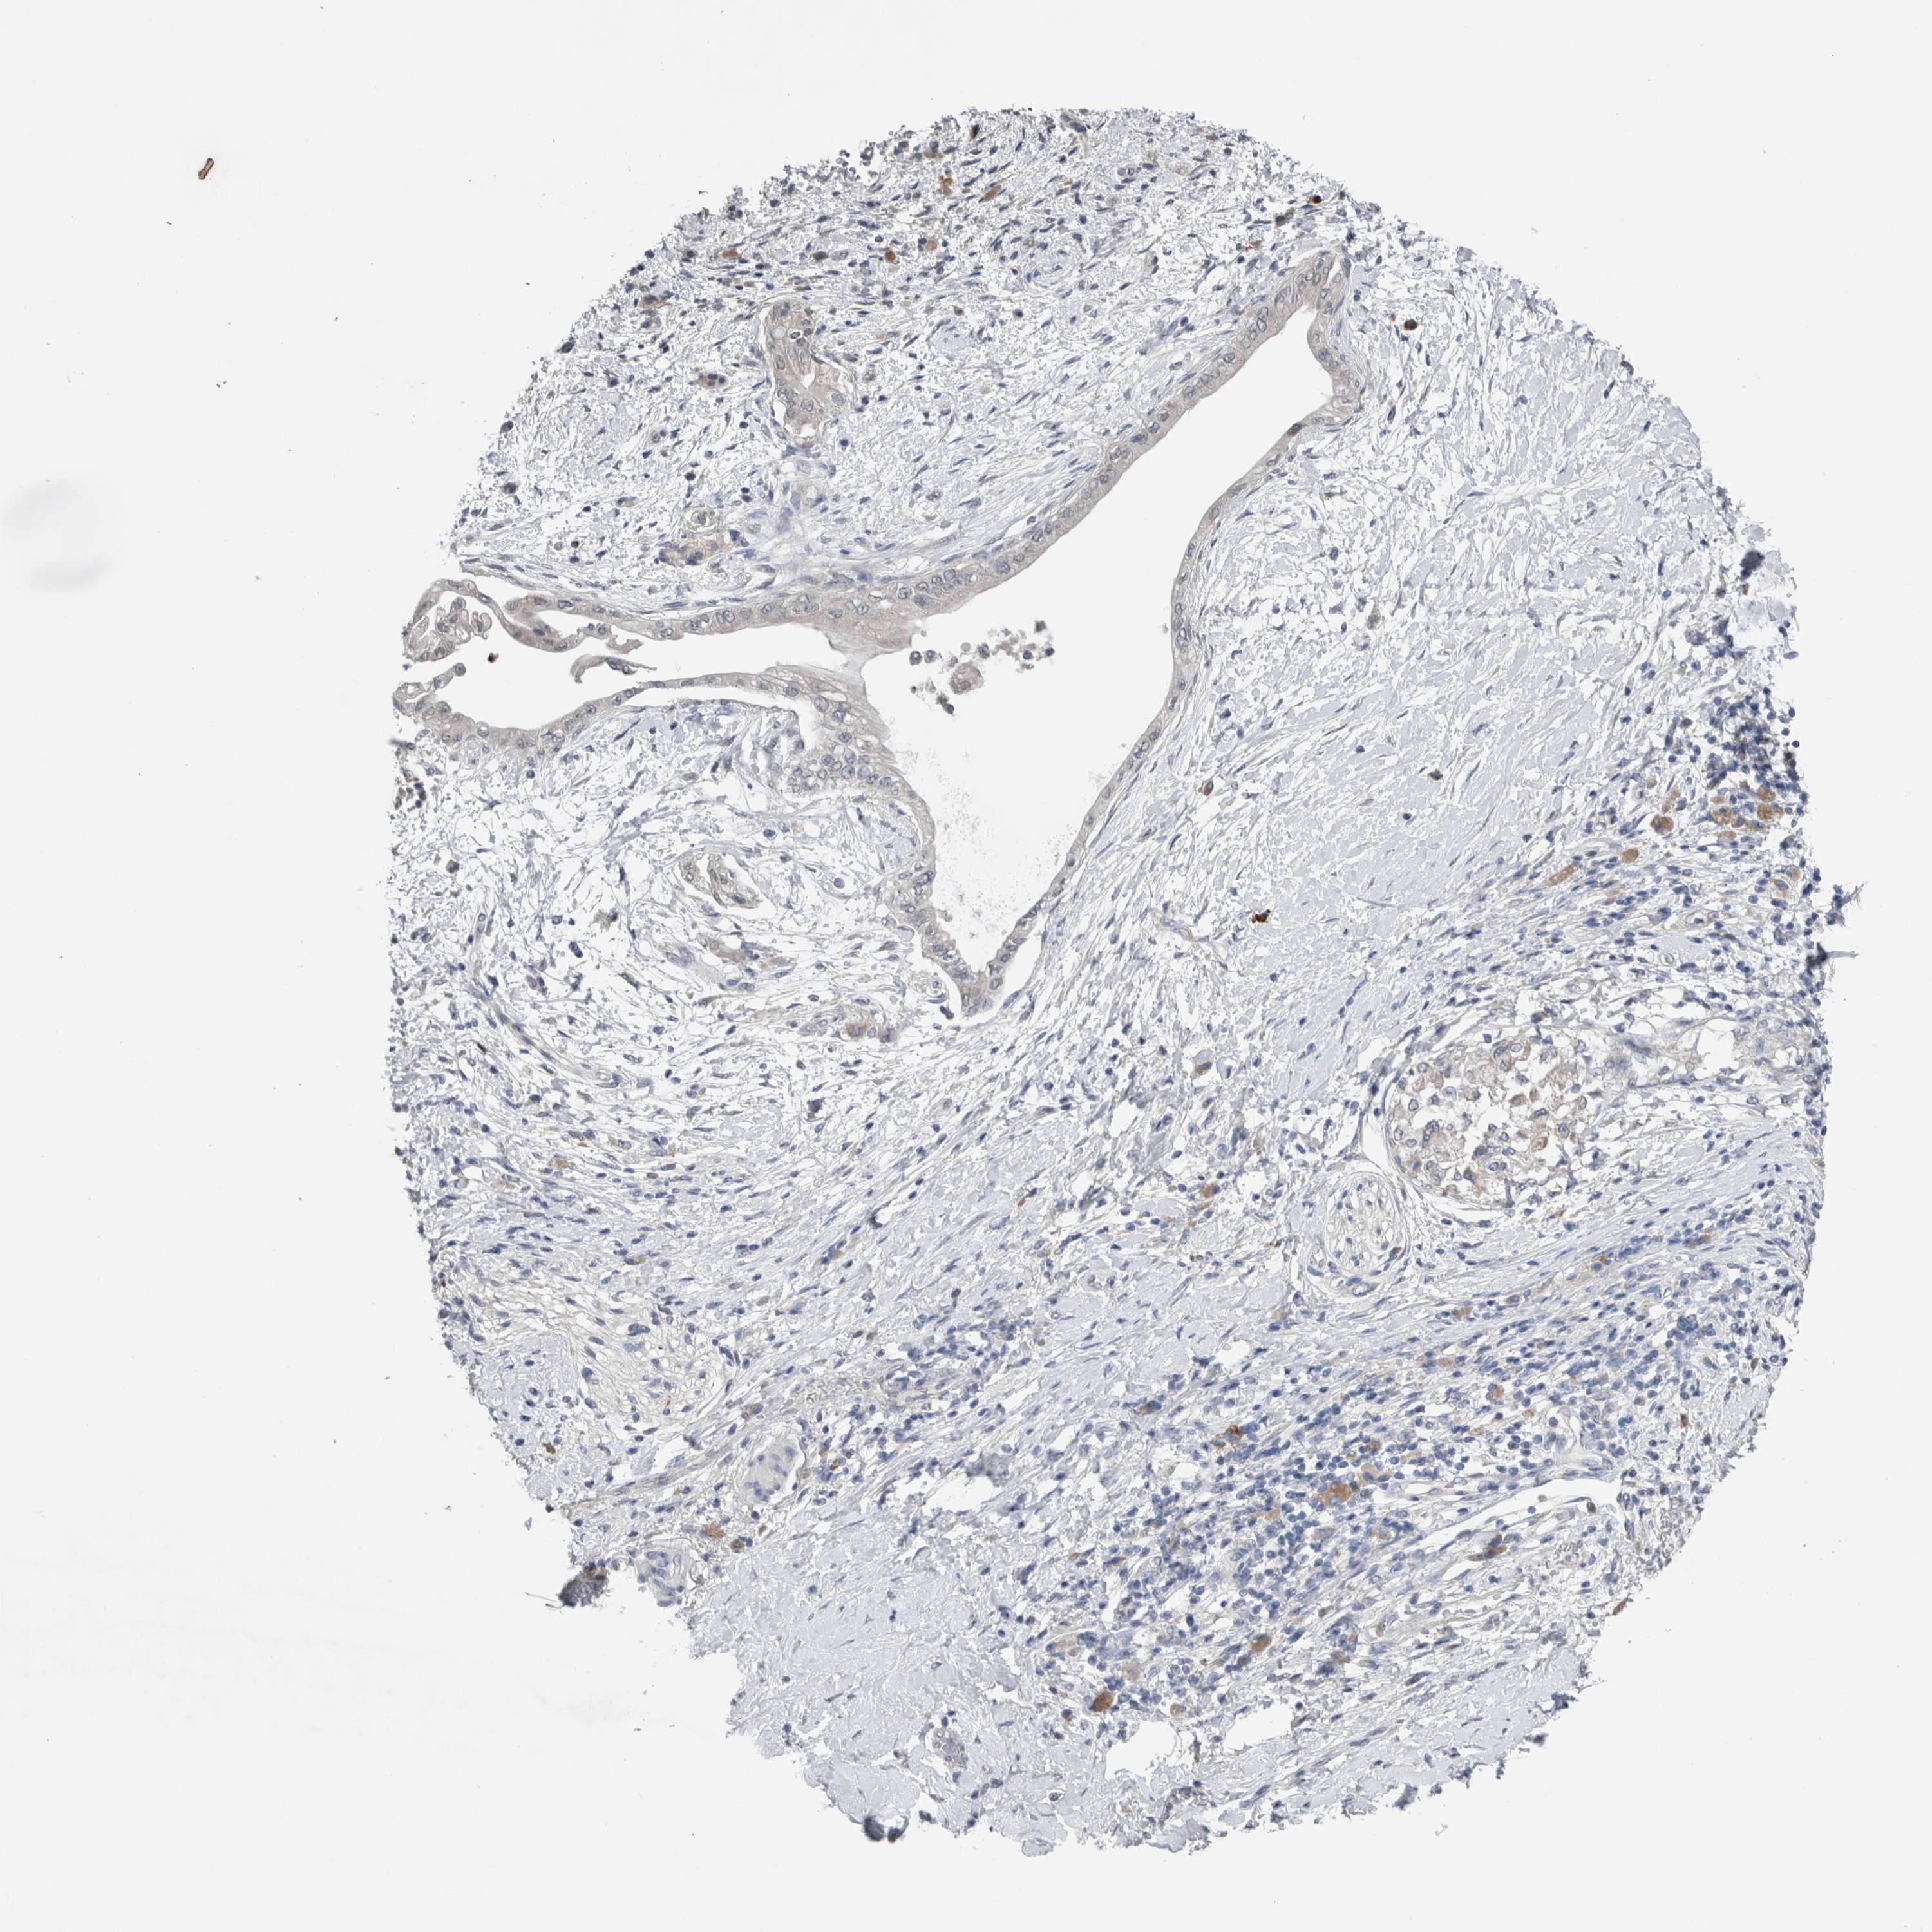

PANCREATIC CANCER - Protein expressioni

A mouse-over function shows sample information and annotation data. Click on an image to view it in a full screen mode. Samples can be filtered based on level of antibody staining by selecting one or several of the following categories: high, medium, low and not detected. The assay and annotation is described here.

Note that samples used for immunohistochemistry by the Human Protein Atlas do not correspond to samples in the TCGA dataset.

Antibody stainingi

Antibody staining in the annotated cell types in the current human tissue is reported as not detected, low, medium, or high, based on conventional immunohistochemistry profiling in selected tissues. This score is based on the combination of the staining intensity and fraction of stained cells.

Each image is clickable and will lead to virtual microscopy that enables deeper exploration of all samples and also displays staining intensity scores, fraction scores and subcellular localization as well as patient and tissue information for each sample.

Antibody HPA024343

Antibody CAB026182

Staining

High

Medium

Low

Not detected

Intensity

Strong

Moderate

Weak

Negative

Quantity

>75%

75%-25%

<25%

None

Location

Nuclear

Cytoplasmic/membranous

Cytoplasmic/membranous,nuclear

Adenocarcinoma, NOS